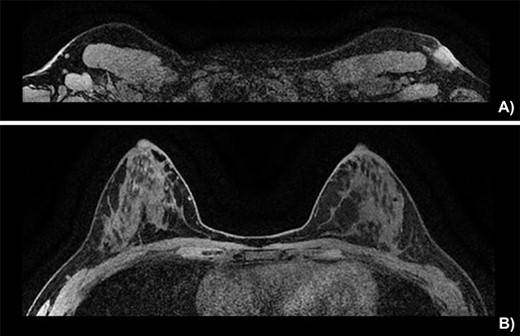

On physical exam, the patient had an area of erythema measuring 4 × 3 cm in the left axilla, with palpable skin thickening and subcutaneous edema (Fig. 1A). An initial mammogram showed an irregular axillary lesion extending to the skin, arising in ectopic breast tissue (Fig. 1A). A subsequent ultrasound showed skin thickening and a spiculated mass measuring 8 mm within the axilla, without any abnormal axillary lymph nodes or breast lesions. Biopsy of the mass demonstrated invasive ductal carcinoma, which was estrogen receptor (ER) positive, progesterone receptor (PR) positive and HER-2 positive. The sample also contained benign mammary gland elements, supporting a tumor localization in ectopic axillary mammary tissue. A magnetic resonance imaging (MRI) study showed no suspicious breast lesions or axillary lymph nodes, and confirmed the known axillary mass with skin extension (Fig. 2). Complete staging by whole-body positron emission tomography (PET) scan and brain computed tomography (CT) scan showed no evidence of metastatic disease.

Breast MRI depicting (A) the known mass in a superficial axillary position with direct invasion of the overlying skin and dermal thickening, measured at 1.8 × 1.3 cm wide by 1.9 cm in height. The left axillary nodes appear more numerous and slightly enlarged but share no malignant features. (B) The left and right breast showing no sign of neoplasia.